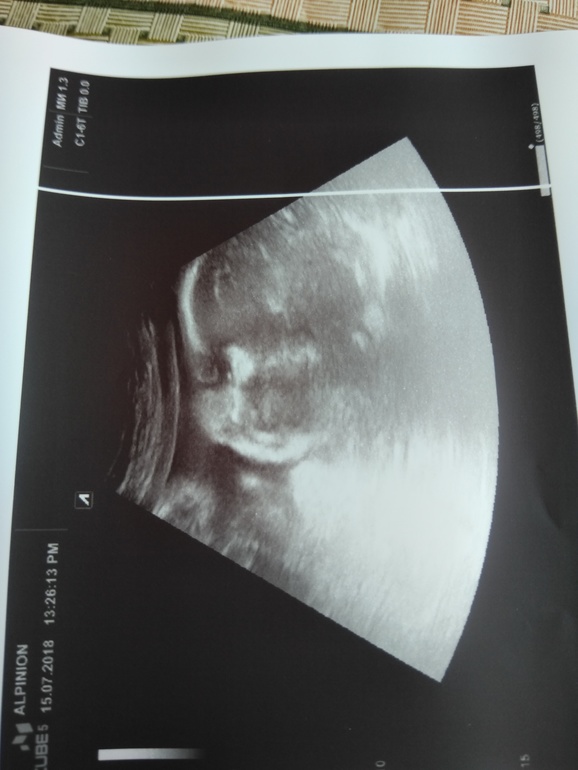

9.07.2018 - 32 недели и 3 дня. Прошли 3й скрининг. Дэн Дэныч немного отстаёт по весу, 1726 грамм. Доктор сказала на 31-32 недели. Зато рост у нас уже 40 см))) зрелость плаценты 2-3, не хорошо, но не критично. Назначили Курантил и Актовегин. Уже хочется родить... Устала от пуза, давления, отеков и ощущения себя старой бабкой. Завтра соберу сумки в роддом. Пусть лежат готовые!

16.07.18- переделали УЗИ на хорошем аппарате. Дэн Дэныч весит 2010грамм. По развитию все хорошо, на 34 недели. А не как 5 дней назад говорили! Опережаем все таки, а не отстаём, и это радует) но плацента все таки даааа... Степень старения 2, кальценаты. Актовегин и Курантил пью, но похоже толку от них будет мало. Отеки опять пришли с жарой и давление поднимается.

P.S. доктор сказал про нас - красивенький щекастик)))